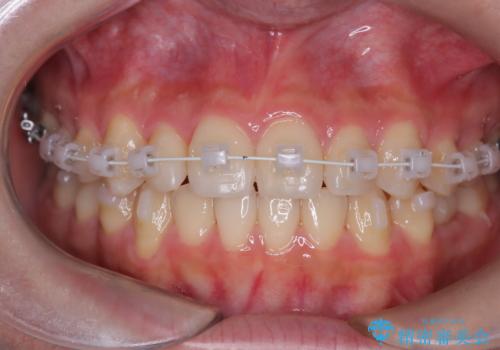

【ワイヤー矯正】インビザラインは途中でやめました

- 矯正装置

- 審美装置

- 前歯の捻れを主訴に来院されました。

インビザラインを希望されておりましたが、20時間もつけることができなかったためワイヤー矯正にて叢生の改善を行っています。

右上の側切歯(前から2番目の歯)が90度程度ねじれている状態でしたが、1月に1回のワイヤー交換できれいに並ぶことができ満足いただけました。

捻れた歯の治療に関しては、ワイヤー矯正の方が仕上がりがきれいに治りやすいです。